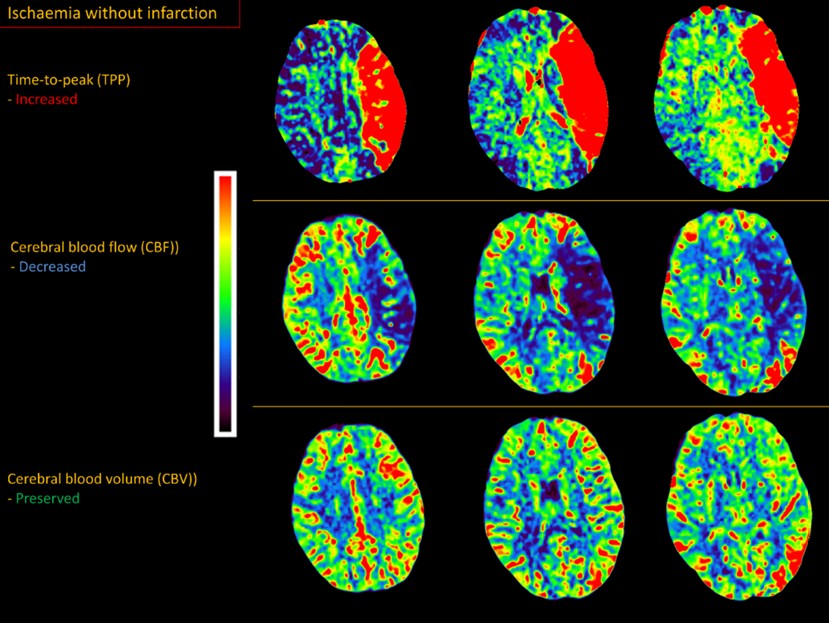

Perfusion imaging indicated a small area of infarcted ‘core’ (30mL) in the deep subcortical white matter, and a large surrounding area of ischaemic, viable, ’penumbra’ (120mL). The ratio of the penumbra to the core - the mismatch ratio - was 4.6. This suggested a large area of brain under threat of infarction but not yet dead, supported by collateral vessels (for now) – amenable to rescue via reperfusion before the collaterals fail. The CT perfusion study is shown below; ischaemia without infarction is shown in the areas with increased time-to-peak (red), reduced cerebral blood flow (blue), but preserved cerebral blood volume (green). They very neatly trace the outline of the MCA territory - showing what a large lesion this is.